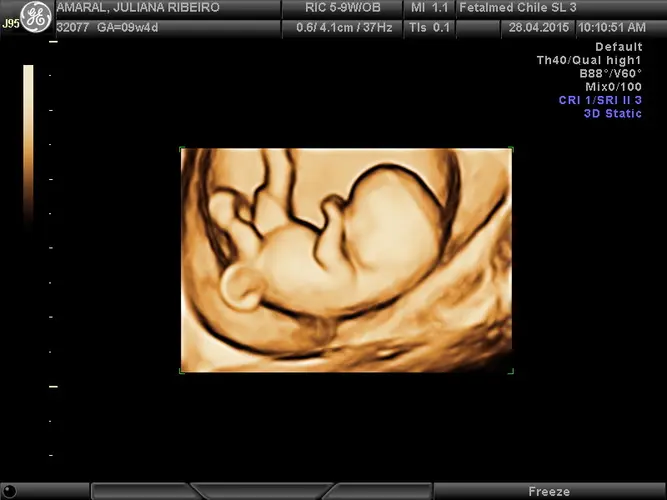

Na 9ª semana de gravidez, seu bebê passou por transformações incríveis. No início desta semana, ele mede cerca de 19 mm e já é possível detectar as primeiras ondas cerebrais – um marco importante no desenvolvimento neurológico. A cabeça continua ganhando proporções mais próximas às de um recém-nascido, enquanto todo o corpinho se desenvolve rapidamente.

Ao final desta semana, seu bebê medirá aproximadamente 25 mm e pesará cerca de 1 grama. A placenta assume uma função ainda mais importante, substituindo o corpo lúteo na produção de progesterona, hormônio essencial para manter a gravidez. Durante uma ultrassonografia, já é possível identificar os primeiros movimentos embrionários, um espetáculo emocionante para os futuros pais.

Dependendo do protocolo do seu médico e da sua situação específica, pode ser solicitada uma ultrassonografia para confirmar a idade gestacional e avaliar o desenvolvimento embrionário. Este exame pode mostrar os primeiros movimentos do bebê e confirmar se tudo está evoluindo conforme esperado para esta fase da gravidez.